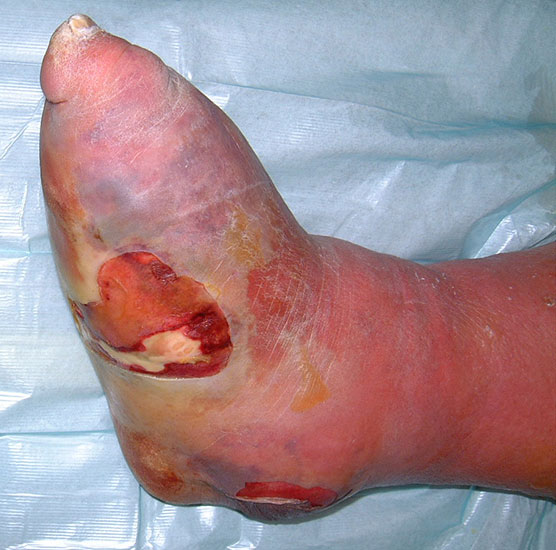

Amputation in der Chopartlinie

Bei der Chopartamputation – (wie auch bei der Amputation in der Bona-Jäger-Linie) – ist zu beachten, dass die Ansätze der Fuß- und Zehenheber entfernt werden, also der Rückfuß durch den Zug des M. triceps surae eine Equinusstellung einnimmt (Abb. 43). Die Folge können hartnäckige Ulzerationen an der Spitze des Stumpfes sein (Abb. 44). Neben der Durchtrennung der Achillessehe (Abb. 45) sollte die plantare, distale Knochenkante abgerundet werden (Abb. 46).